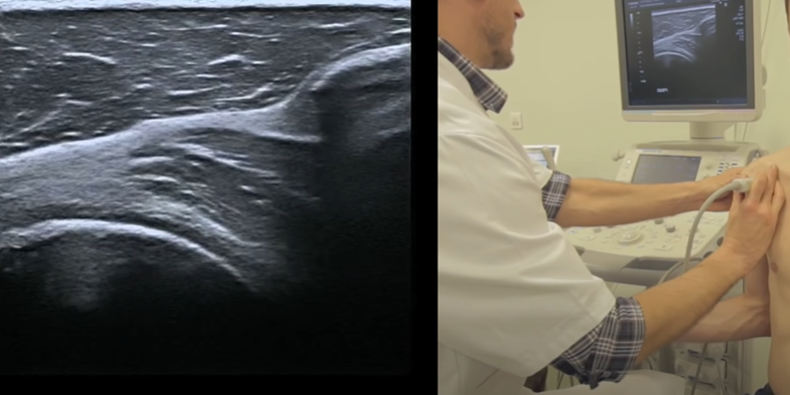

- Manoeuvres dynamiques en axial (ouvrir et fermer l’épaule, regarder le comportement du tendon sous le coracoide

Manoeuvres dynamiques rotation

Coupe axiale avec les fasiceaux